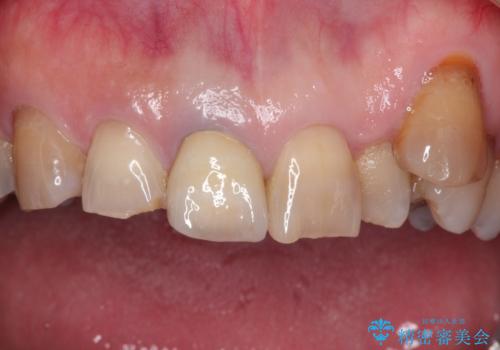

セラミックによる前歯の変色の改善

オールセラミックを装着することで改善することとしました。

他の歯になじむ色を選択することで、自然な仕上がりにすることができました。